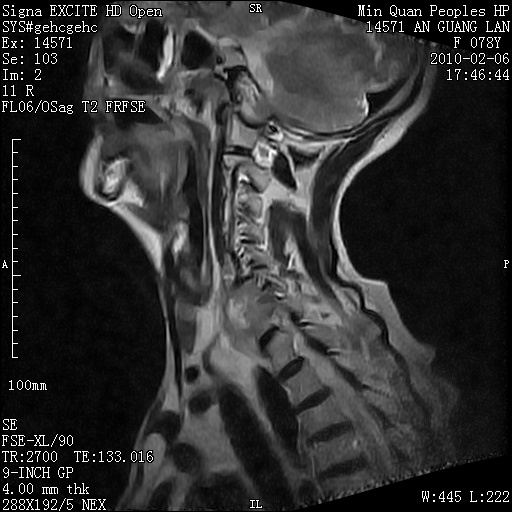

标题: MRI2763:C6、C7椎体病变性质?

f,78y,颈部与双上肢阵发性剧痛40余天。ct可见c6、c7椎体虫蚀样破坏,其间椎间隙变窄(没有图片资料可供上传)。

考虑椎体结核并椎旁脓肿。

支持 c6、7椎体结核并椎旁冷脓肿形成。

考虑:c6/7椎体结核并椎旁脓肿形成,建议增强扫描。

单从影像表现此诊断不难,还应该结合临床资料排除其他